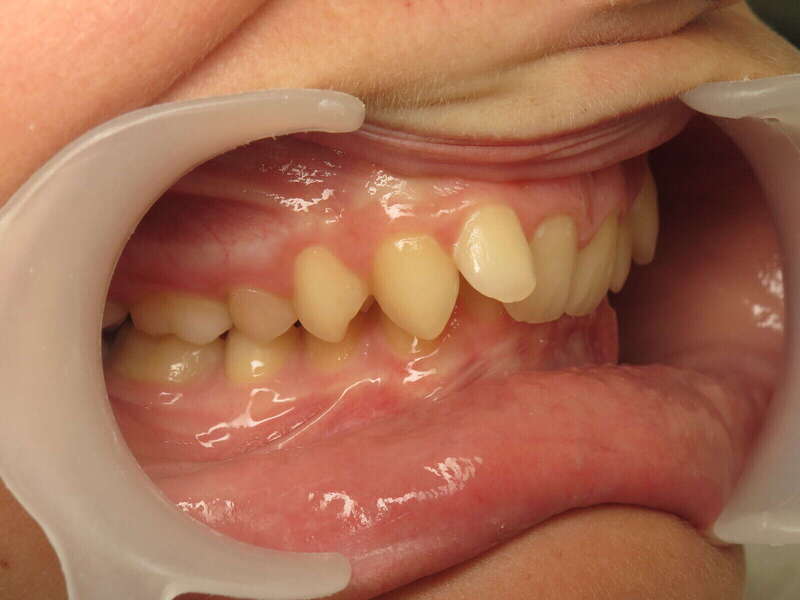

Cas n°1 traité par aligneurs (interception) - enfant

Ce cas d’interception chez un enfant de 8 ans démontre l'efficacité des aligneurs pour corriger des troubles fonctionnels précoces. Le diagnostic présentait des inversions d'articulé provoquant une déviation de la mandibule vers la gauche et un décalage des milieux.

Grâce à une coopération exemplaire et un traitement totalement indolore, l'expansion de l'arcade a permis de recentrer la mâchoire. Cette intervention a littéralement remis la croissance sur les rails, neutralisant le risque d'asymétrie faciale squelettique.

Avant

Après